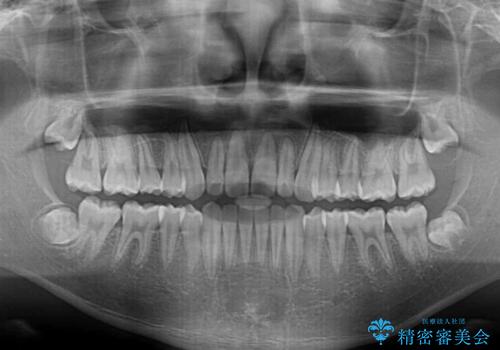

中学生のワイヤー矯正 クロスバイトを短期間で改善

- 前歯のクロスバイトを気にして来院された患者様です。

中学生であることから、治療期間を短縮できると判断し、ワイヤー矯正にて短期間で治療を行うこととしました。

叢生のため磨き残しの多い歯列でしたが、1年弱で治療を終了でき、磨き残しや歯肉の腫れが著しく改善されました。